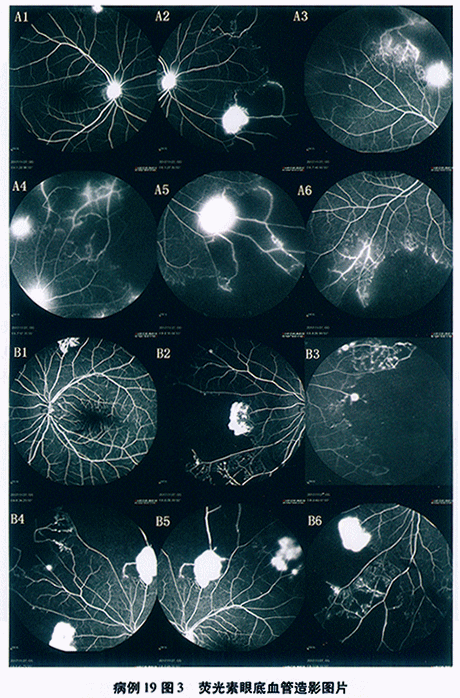

FFA(2013-7-31,本院): 双眼视网膜动静脉充盈时间正常范围,视网膜后极和中周荧光轻度渗漏, 视乳头荧光渗漏,边界模糊——考虑“双眼葡萄膜炎? ”(见图39-5)